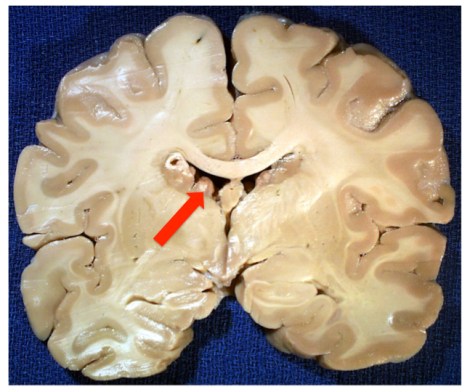

A coronal section of a brain from someone with Tuberous Sclerosis, a syndromic form of autism that is usually a result of a loss-of-function mutation in either the TSC1 or TSC2 genes and which causes upregulation of mTOR pathway activity, leading to increased cell growth and proliferation. In this case, you can easily see the tuberous growths lining the lateral ventricles. Image borrowed from here.

Except in the case of an ongoing neoplasia, the tubers in Tuberous Sclerosis only arise during that GD 40-120 day period. And the same can be said of nonsyndromic autism. And so what do we find in the majority of cases of autistics? We find evidence of hyperplasias in the form of increased minicolumnar numbers, focal dysplasias, and heterotopias, the latter which are neurons which have failed to migrate properly and are located inappropriately in either the gray or white matter [1, 2, 3]. (Because precise timing of proliferation is vital for newborn neurons to receive their proper cues for differentiation and migration, being born at the “wrong time” can lead to miscommunication and the stranding of cells along their developmental and migratory paths.)